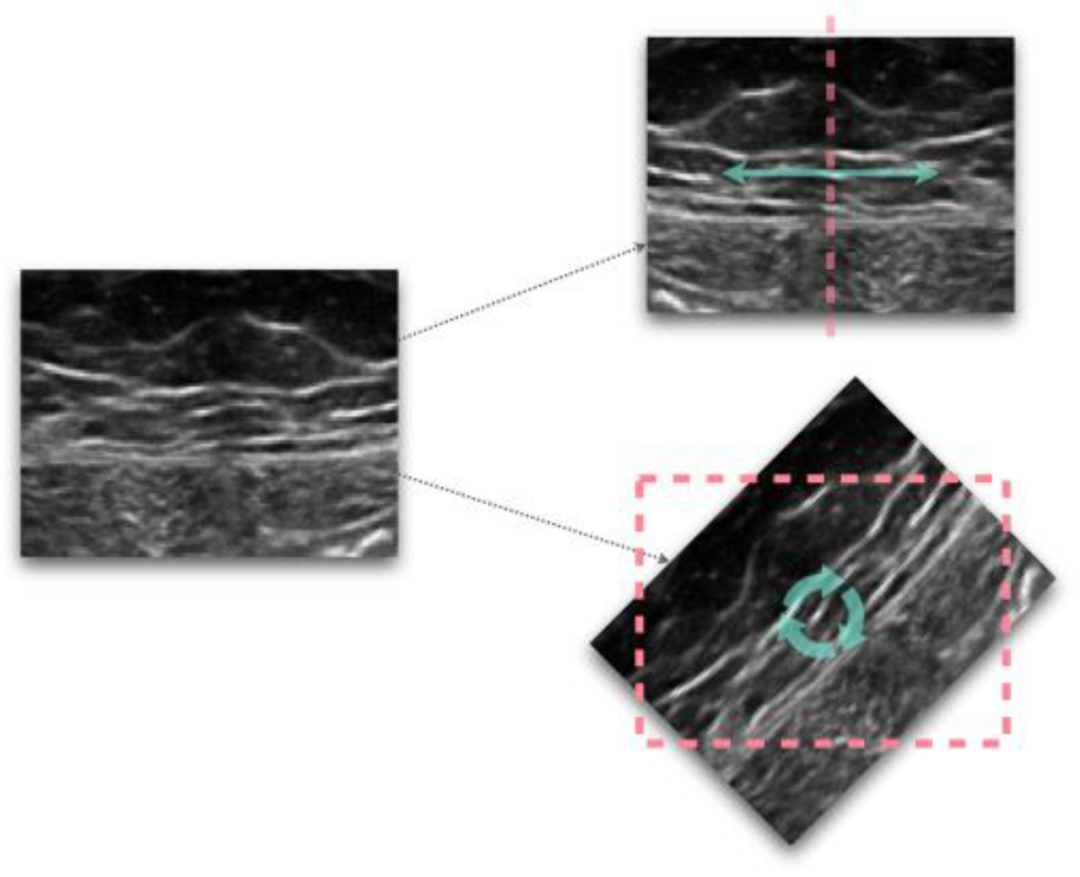

數(shù)據(jù)增強,即人為增加訓(xùn)練樣本數(shù)量,通常用于解決過擬合問題和提高網(wǎng)絡(luò)效率。

最近的數(shù)據(jù)增強技術(shù)還包括各種生成方法。其中,生成對抗網(wǎng)絡(luò)(GAN)是一種深度學(xué)習(xí)方法,它識別了數(shù)據(jù)集的內(nèi)在分布,并利用它生成逼真的合成樣本。對于分辨率低、圖像偽影或由于不同掃描儀采集而引起的變化等樣本,數(shù)據(jù)增強過程還具有增加模型穩(wěn)健性的優(yōu)勢。

圖1 圖像變換的示例,翻轉(zhuǎn)(頂部)和旋轉(zhuǎn)(底部)